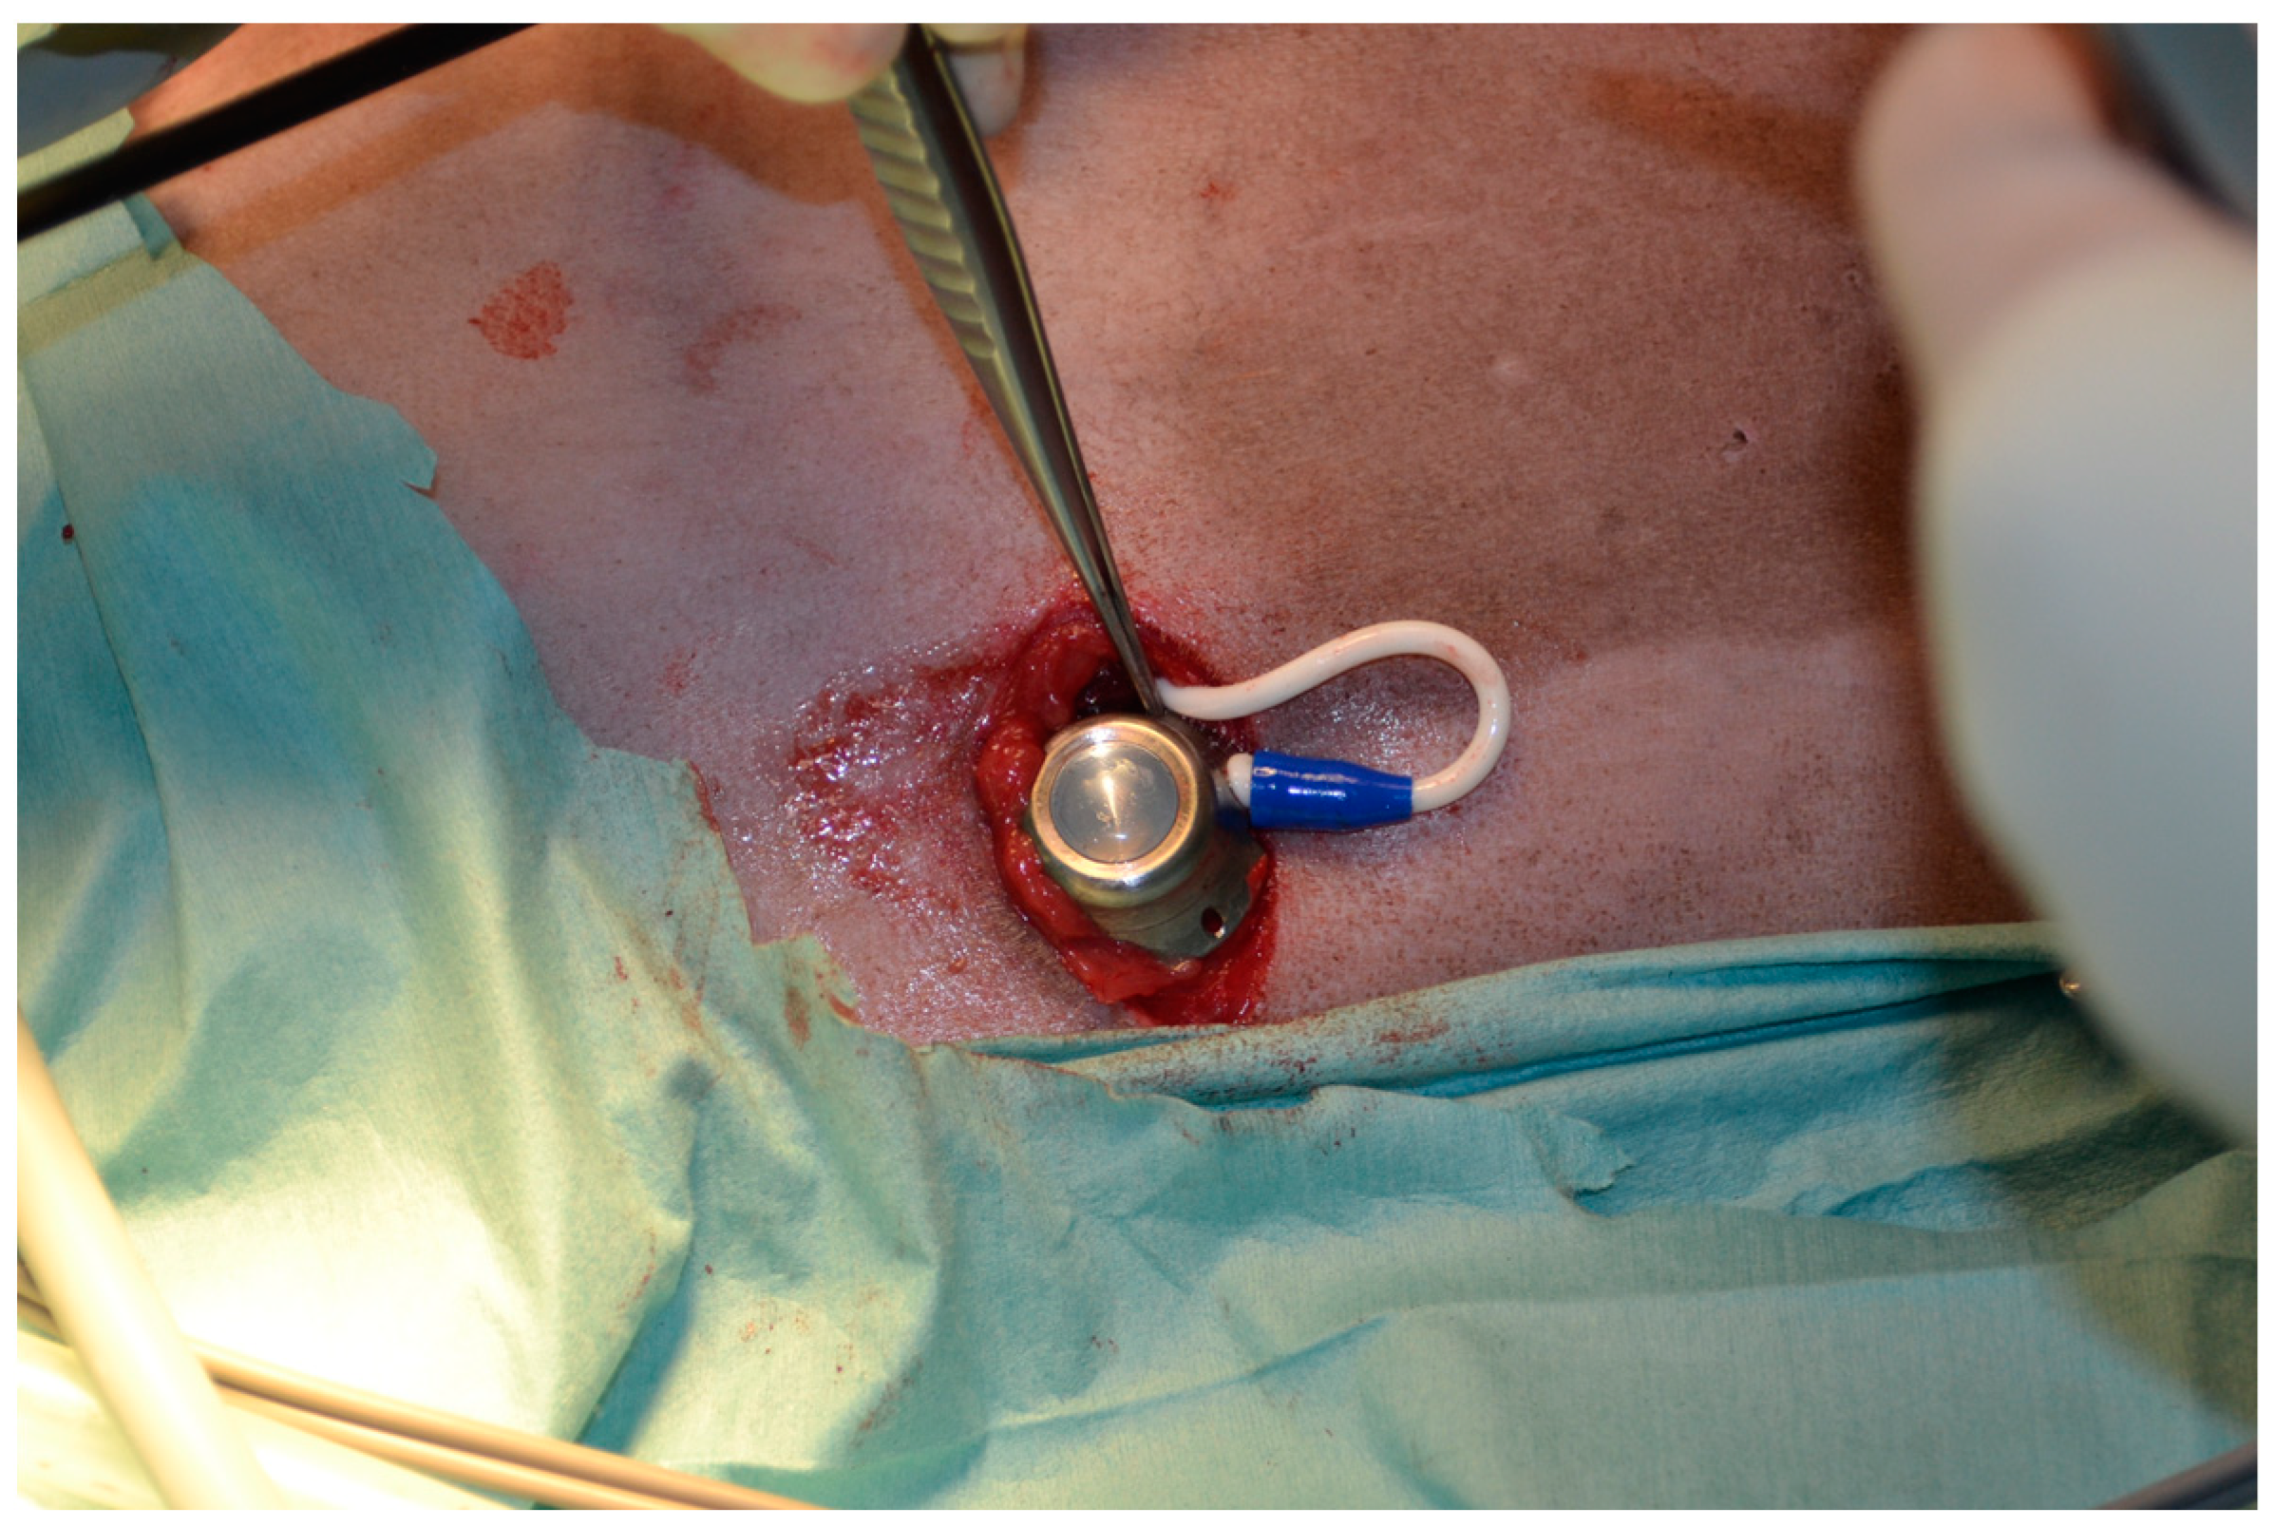

2.1. Surgical Procedure